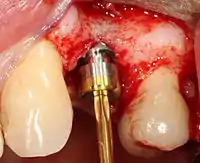

2. الحفر بسرعة عالية: بعد عكس الأنسجة الرخوة، واستخدام دليل جراحي أو دعامة حسب الضرورة، يتم وضع ثقوب تجريبية بإستخدام أداة دقيقة تعمل بسرعة منظمة مع خاصية تبريد ذاتية لمنع حرق أو نخر العظام.

3. الحفر بسرعة منخفضة: يتم توسيع الفتحة الأولية التجريبية باستخدام أدوات حفر أعرض تدريجيًا (عادةً ما بين ثلاث وسبع خطوات حفر متتالية، اعتمادًا على عرض الزرعة وطولها ونظام عملها المحدد من الشركة المنتجة لها). يتم الحرص على عدم إتلاف خلايا العظام من خلال ارتفاع درجة الحرارة لذلك يلحق الأداة بمحلول تبريد أو رذاذ ماء.

4. وضع الغرسة: يتم وضع برغي الزرع ويمكن أن يكون من النوع الذي يتم دورانه واحتواءه في العظم ذاتيًا . ثم يتم تثبيته في مكانه باستخدام مفتاح تحكم ينتج دوران بعزم دقيق حتى لا تتأثر العظام المحيطة (حيث أن يمكن أن يسبب تنخر العظم، والتي قد تؤدي إلى فشل الغرسة في الالتحام الكامل أو الترابط مع عظم الفك).